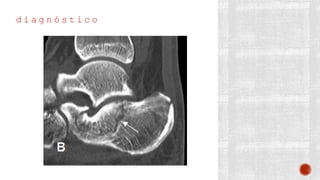

d i a g n ó s t i c o

¬ Clínico

¬ Radiológico

- AP de tobillo

- Lateral de tobillo

- De mortaja

- AP de pie

- Lateral de pie

- Oblicua de pie

- Proyección de Canale

- TAC

- Gammagrafía ósea con tecnecio 99

- RM